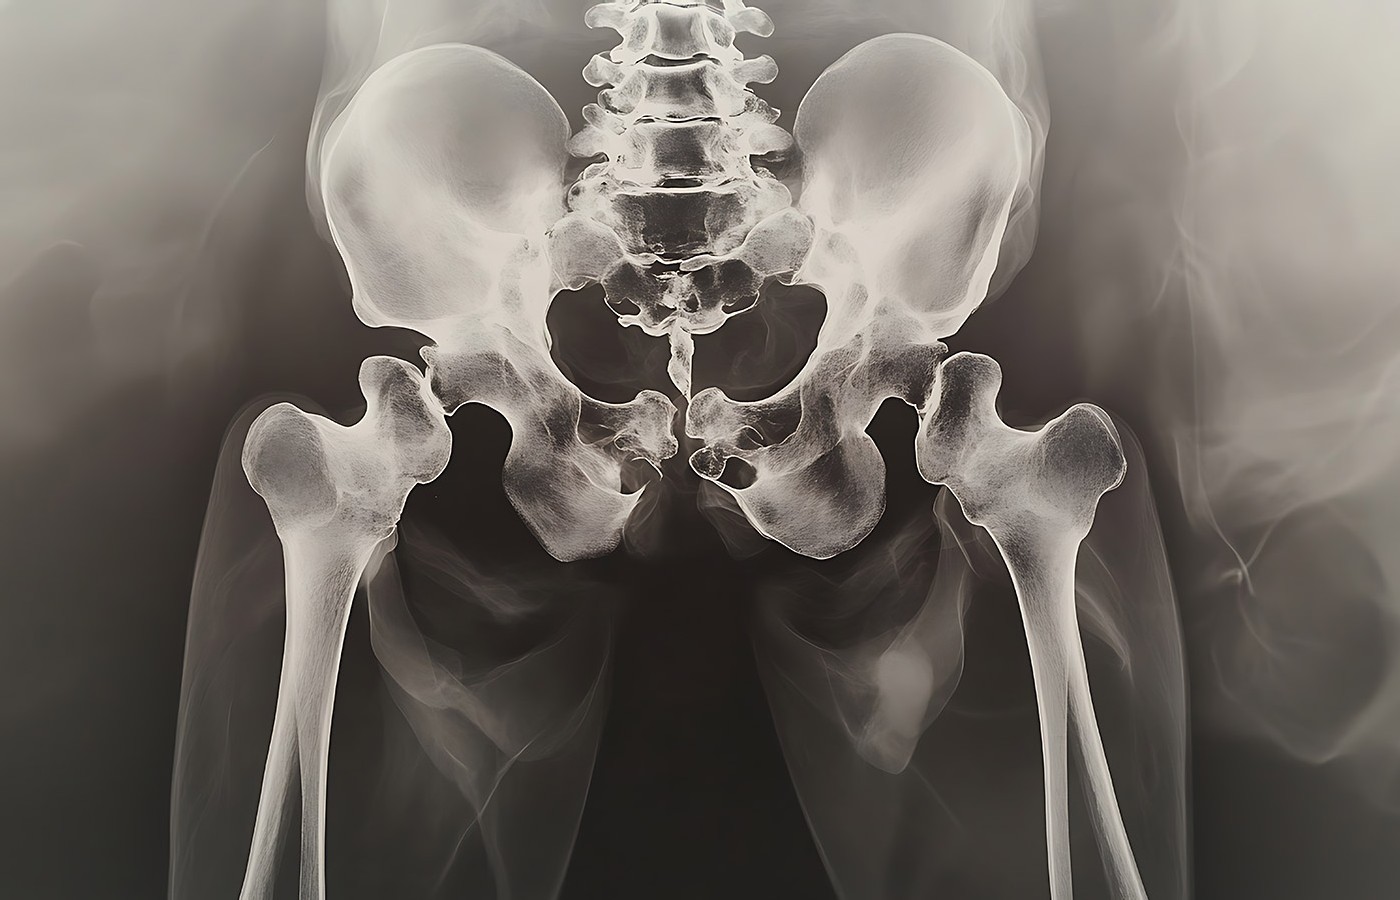

Pain in the lateral hip provoked by physical activity and palpation is now termed greater trochanteric pain syndrome. In addition, MRI and diagnostic ultrasound of these patients demonstrate gluteal tendinopathy (gluteus medius and minimus especially) is present; however, concomitant bursitis s found in fewer than 30% of the cases. In addition, less than 3% of patients with trochanteric pain actually have isolated trochanteric bursitis.

Myth Buster #1: Localized lateral hip pain is rarely due to an inflamed trochanteric bursa. It is most likely a tendinopathy of the gluteus medius and minimus tendons.